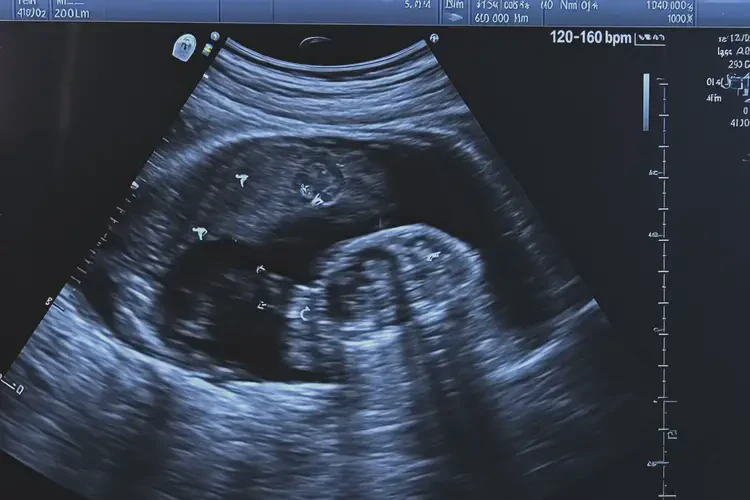

胎心率160次/分钟在正常范围内,宝宝可以要。

怀孕七个多月时,胎心率在160次/分钟是正常的。胎心率是指胎儿心脏每分钟跳动的次数,通常在120-160次/分钟之间被认为是正常范围。胎心率可能会受到多种因素的影响,包括胎儿的活动水平、母亲的情绪和身体状况等。单次胎心率测量结果并不能完全反映胎儿的健康状况。

胎心率的正常范围是120-160次/分钟。在这个范围内,胎儿的心脏功能是正常的。影响因素